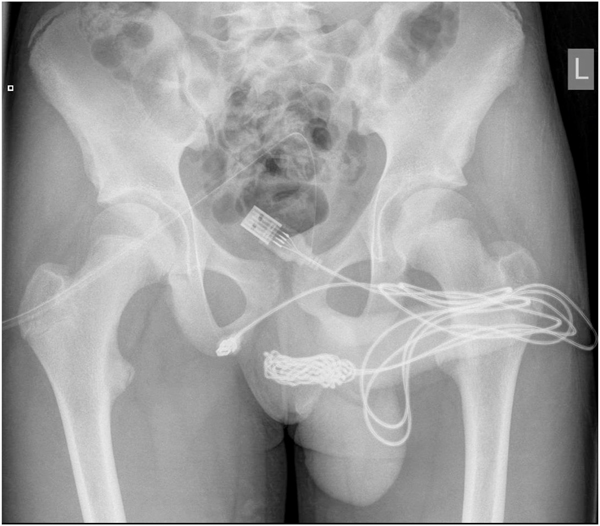

ผลการเอกซเรย์เผยให้เห็นว่าสายไฟเข้าไปพันเป็นปมแน่นอยู่ภายใน หมอต้องทำการผ่าบริเวณระหว่างอวัยวะเพศกับทวารหนัก โดยตัดนำส่วนที่เป็นปมออกมาก่อน จากนั้นจึงนำสายไฟส่วนอื่น ๆ ที่ค้างอยู่ออกมา